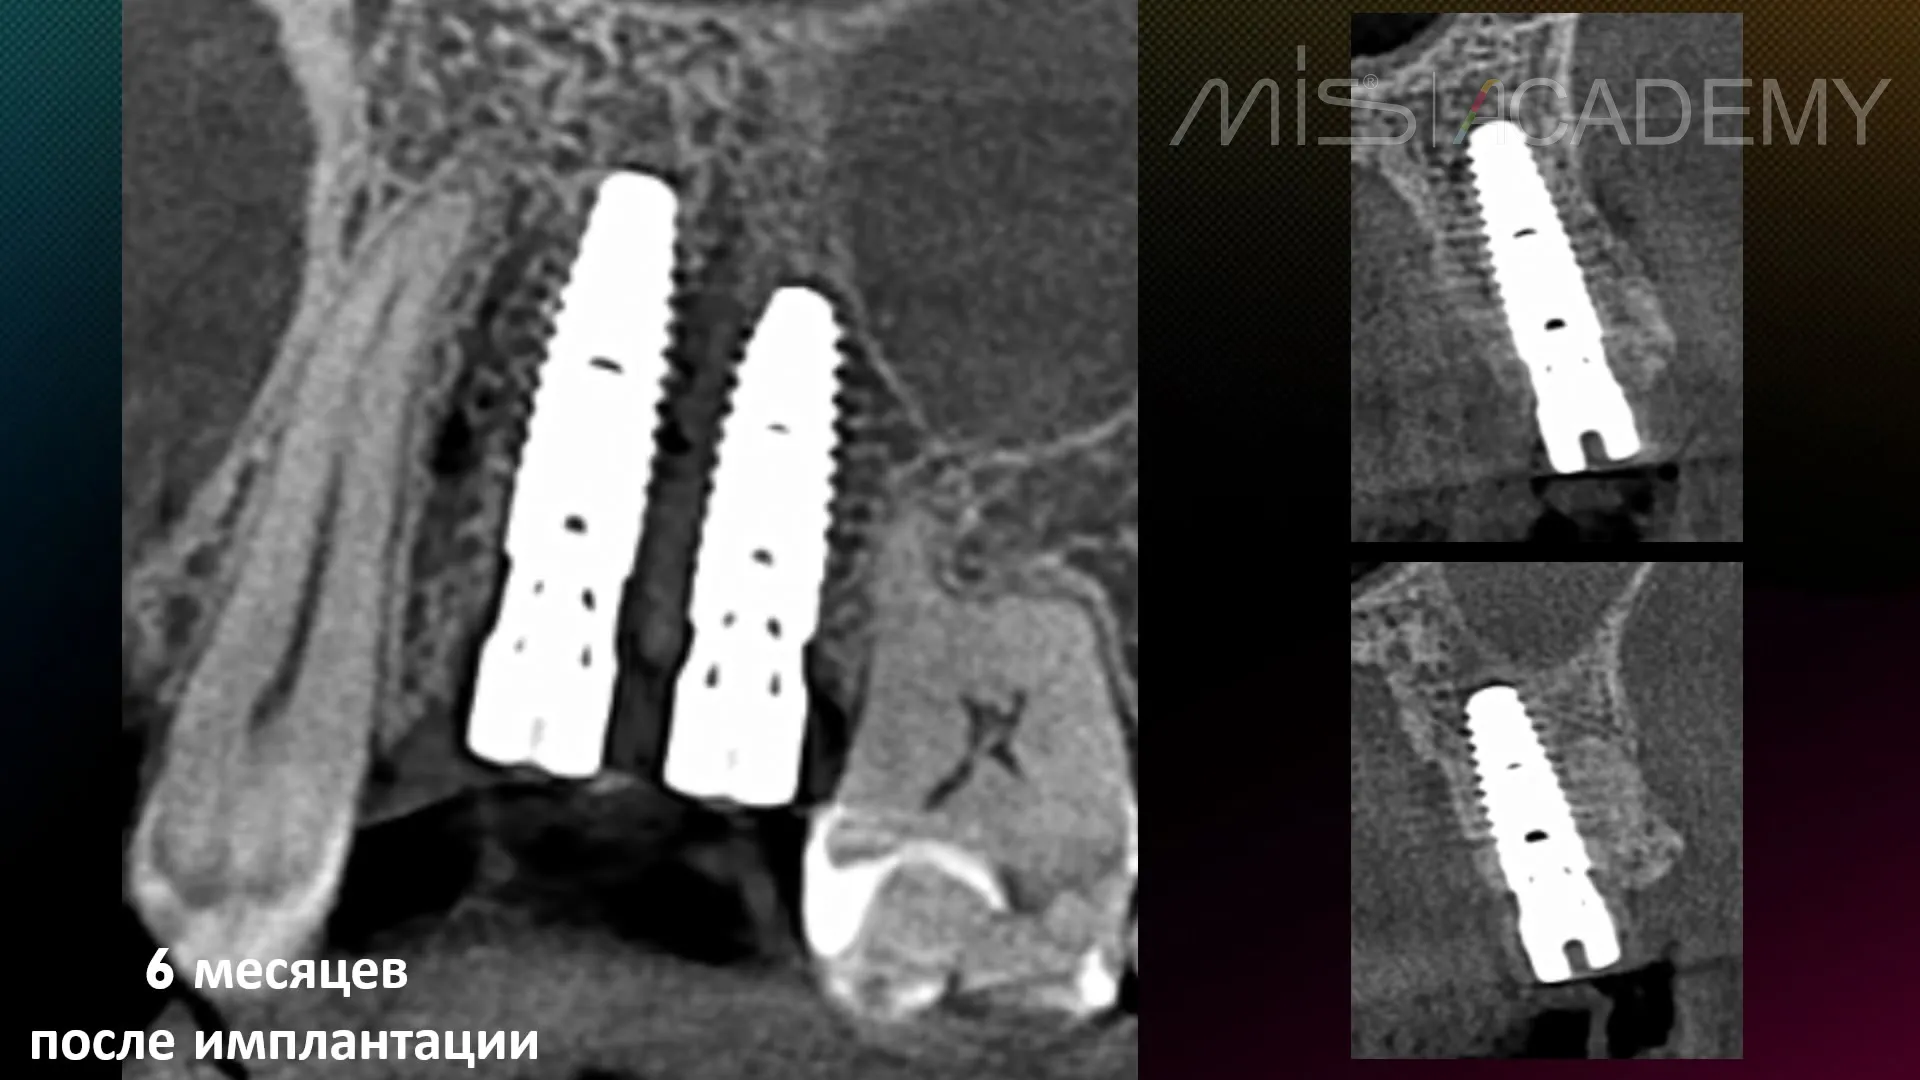

— Временные коронки через 6 месяцев.

— Результат формирования контура прорезывания на временных коронках спустя 1 месяц после их установки.